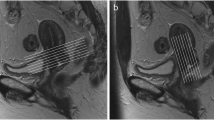

Pretreatment clinical prognostic factors (CPF: FIGO stage, lymph node status and histological type) and MRI parameters of post-treatment non-residual and residual tumour groups in patients with cervical cancer are shown in Table 1. At one month after CCRT completion, 44 of 65 patients had no residual tumours, and the remaining 21 women had residual tumours on MRI. There was a significantly higher FIGO stage in residual tumours than in non-residual tumours (p < 0.001). No significant differences in lymph node status and histological type were found between the two groups (p = 0.629 and p = 0.955). Lower pretreatment MSI and SER in low-perfusion subregions (0.47 ± 0.33 vs. 1.37 ± 0.87, p < 0.001; 0.76 ± 0.32 vs. 1.02 ± 0.28, p = 0.003, respectively) and a significantly higher ADC value (1.10 ± 0.23 vs. 0.84 ± 0.11, p < 0.001) were found in post-treatment residual tumours than those in non-residual tumours. However, MSI and SER in high-perfusion subregions and tumour size were not significantly different between the two groups (p = 0.32, p = 0.33, and p = 0.078, respectively; Table 1 and Fig. 1).

MR images of a 63-year-old woman with cervical squamous cell carcinoma of stage IIB before concurrent chemoradiotherapy. Axial T1-weighted imaging and sagittal T2-weighted imaging (a and b) show the tumour with an irregular heterogeneous iso- and hyperintensity in the uterine cervix (arrow). Axial diffusion-weighted imaging (c) shows the tumour with an obvious hyperintensity (arrow). Corresponding ADC map (d) shows a decreased ADC value. Sagittal dynamic contrast-enhanced MRI (e) shows the tumour with obviously heterogeneous enhancement. Corresponding time-signal intensity curves (f) of regions of interest (ROIs) show persistent and slow increase in low-perfusion subregions of the tumour (ROI1) and show a rapid increase and a persistent plateau in high-perfusion subregions (ROI2)